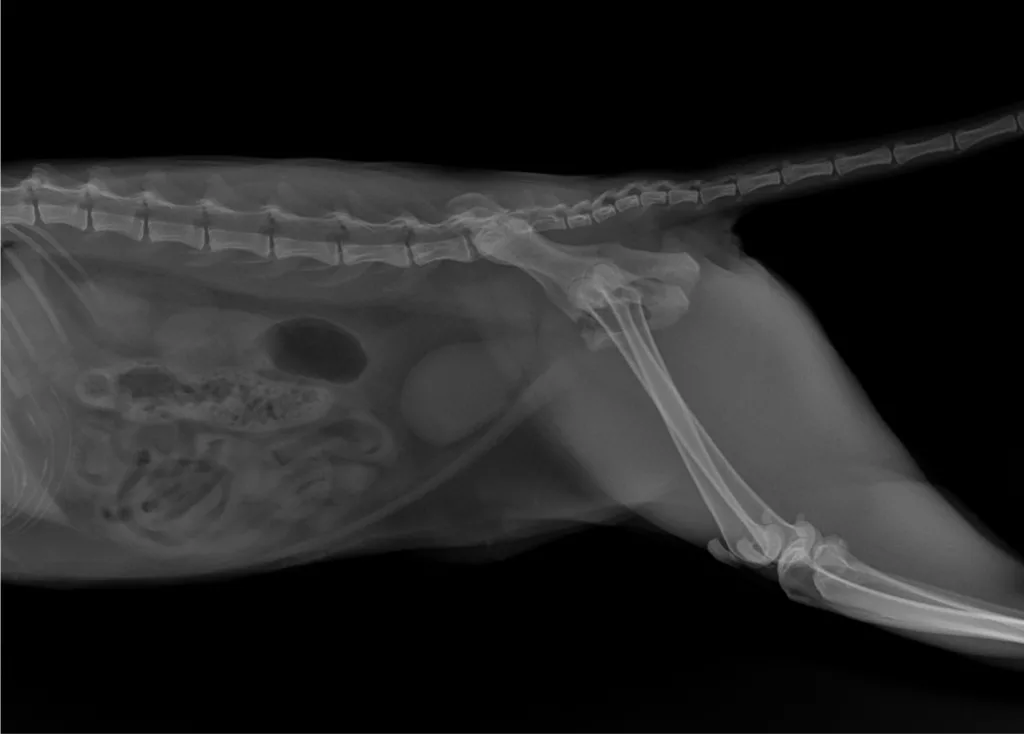

Infelizmente, ela sofreu uma fratura no quadril e, desde então, não consegue se locomover ou apoiar os membros posteriores, provavelmente sentindo muitas dores.

Atualmente, ela está hospitalizada no Hospital Veterinário Benevet, onde recebe os cuidados necessários. No entanto, para que ela volte a andar, é indispensável realizar uma cirurgia. O problema é que os custos do procedimento e do tratamento são muito altos, e, neste momento, os tutores não têm condições de arcar com o valor.